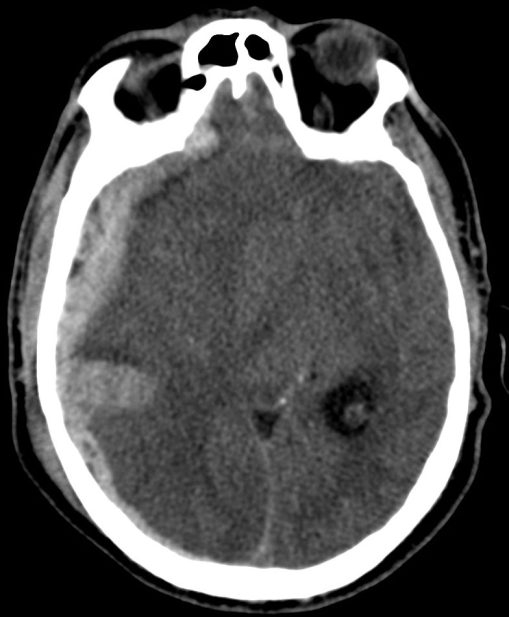

1- Edema cerebral difuso: Aparece en las primeras 48 horas del traumatismo. Se identifica por:

- Produce efecto de masa.

- Borramiento de surcos = pérdida de la interfase sustancia gris-sustancia blanca.

- Otros: signo del cerebelo blanco, falsa hemorragia subaracnoidea…

Transtentorial: puede ser unilateral/uncal o bilateral/central.

- Por descenso del contenido supratentorial a través de la tienda del cerebelo.

- Puede ser unilateral o Uncal = descenso del uncus hacia el interior de la cisterna supraselar.

- Bilateral o Central = obliteración las cisternas basales